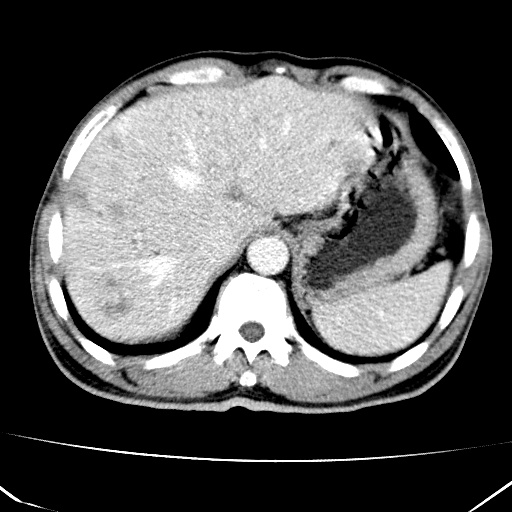

标题: CT17975:请求会诊。男、57岁。上腹部胀痛2天。临床诊断:糜 [打印本页]

标题: CT17975:请求会诊。男、57岁。上腹部胀痛2天。临床诊断:糜

肝脏多发类圆形低密度影,考虑肝脏转移瘤,肝胃韧带一淋巴结肿大,原发?胃癌?

考虑胃癌并肝脏及腹膜后淋巴结转移;不排除淋巴瘤。

肝内转移瘤,腹腔及腹膜后淋巴结转移。